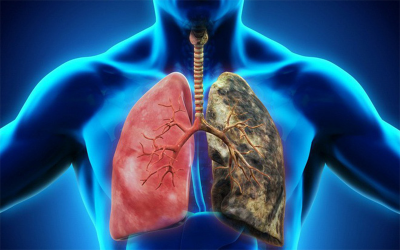

Hiểu biết về viêm phổi với ung thư phổi

Viêm phổi là một bệnh nhiễm trùng phổi phổ biến. Nguyên nhân có thể do vi khuẩn, vi rút hoặc nấm. Nếu bị ung thư phổi, bạn sẽ có nguy cơ cao mắc bệnh viêm phổi. Bài viết này...

Hiệu quả của hóa chất Pemetrexed trong điều trị ung thư phổi không tế bào nhỏ giai đoạn muộn

Ở Việt Nam, phần lớn ca ung thư phổi được phát hiện muộn nên hiệu quả điều trị còn khá thấp. Những năm gần đây, hóa chất Pemetrexed trong điều trị ung thư phổi không tế bào nhỏ giai đoạn muộn đã đem lại nhiều kết quả...